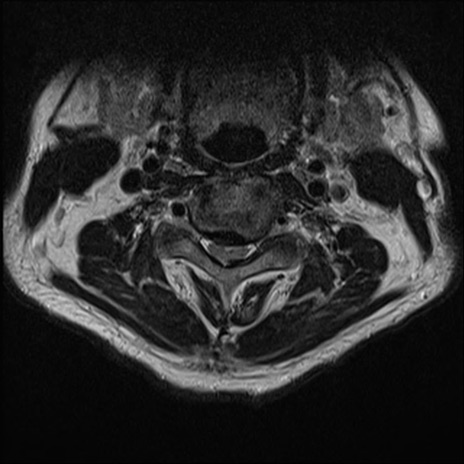

【整形】TIPS症例7 頚椎MRI T2WI(横断像)

頚椎MRI

矢状断像と横断像